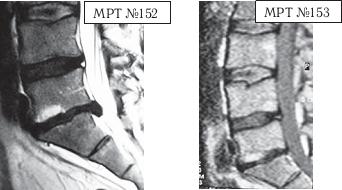

МРТ № 4

МРТ № 5

На МРТ № 4 наблюдается межпозвонковый диск в начальной стадии развития дегенеративно-дистрофического процесса.

На МРТ № 5 наблюдается межпозвонковый диск на более поздней стадии развития дегенеративно-дистрофического процесса.